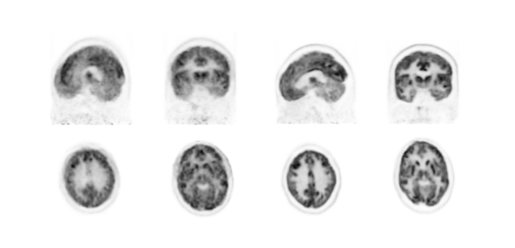

Clinical image based on a device's Clinical image based on MinFound ScintCare

PMT-PET analog detector PET/CT 730T SiPM digital detector